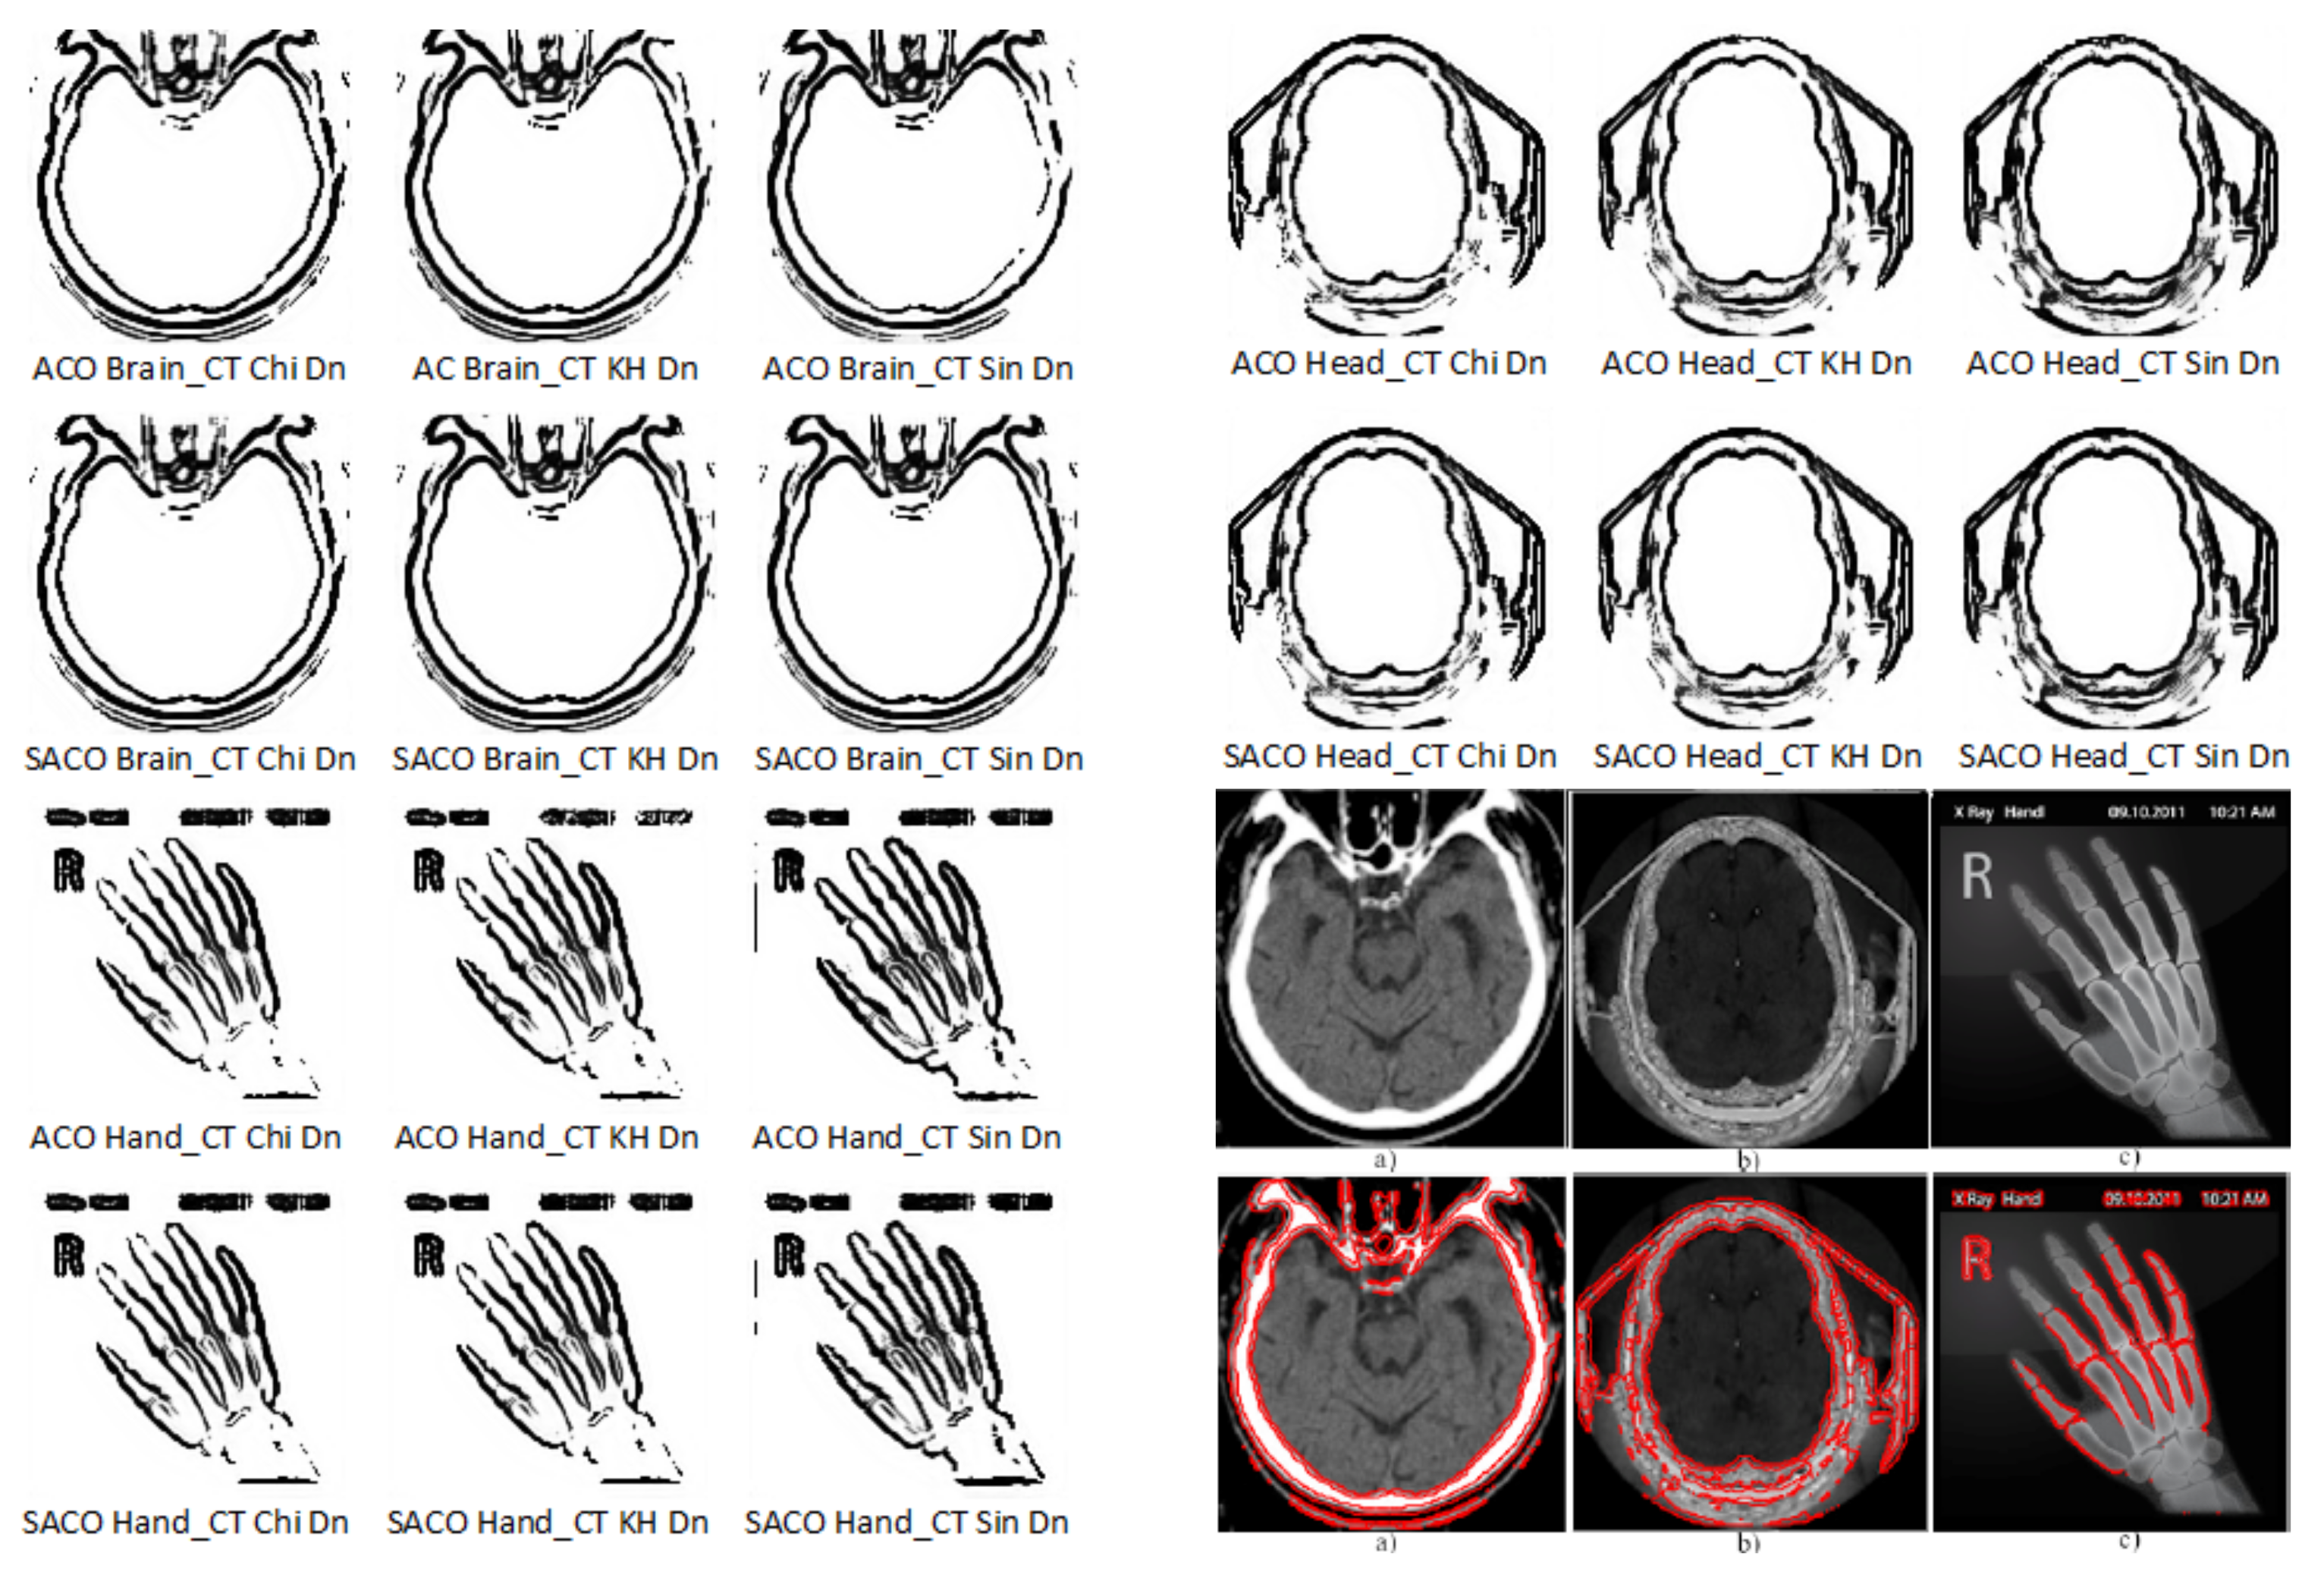

- An operator comparison analysis based on Figure 3 uses the difference of SACO vs. ACO values; for the Sin-operator, the difference has a majority of negative values, with ACO obtaining better values than SACO for the considered operators (44.45%); for the other two operators, χ-operator (Chi) and KH-operator, 77.78% shows SACO performing better than ACO on the 9 considered cases of medical images;

- Medical image analysis. For each medical image, including head CTs, brain CTs and hand X-rays, Figure 3 identifies operators’ behavior on the difference between SACO and AC0. The lowest SACO performance, 44.44%, was obtained for the head CT medical images; its highest performance was 100% for the brain CT images, while for the hand X-rays, a 55.56% performance value was obtained. The percentage is based on the number of considered medical images.